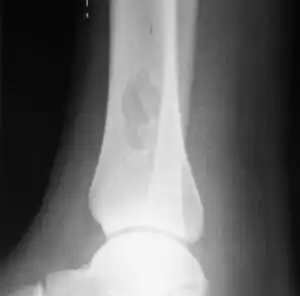

| X-ray of nonossifying fibroma of distal tibia. | |

1. b. Side view X-ray: NOF of the lower leg bone near ankle, with well-defined tumor -